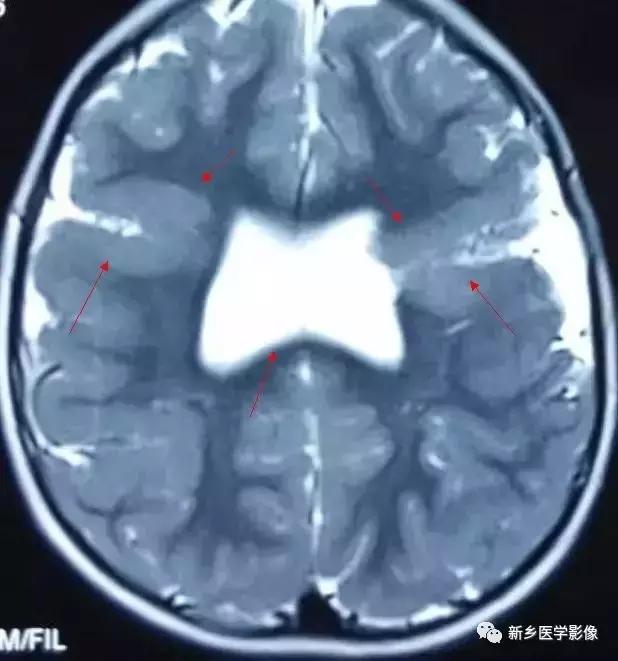

(3)无脑回和巨脑回

无脑回和巨脑回是一组因神经元移行异常所致的脑回发育异常。巨脑回也称平滑脑。巨脑回指有部分脑回存在,这些脑回异常增大增宽.脑沟变浅。巨脑回主要位于额、颞部。无脑回上要位于顶、枕部。

临床上,无脑回和巨脑回畸形患儿均表现有小头畸形和轻微的面部异常,完全无脑回畸形常在两岁前死亡.不完全无脑回畸形存活常能长期。

CT和MR均能够很好显示无脑回和巨脑回畸,表现为大脑半球表面几乎呈光滑状,仅可见少数宽阔、粗大、平坦的脑回,脑沟缺如.脑灰质增厚,脑白质变薄,灰白质分界面异常平滑,见不到白质向灰质内伸入的现象。常见透明中隔腔存在.侧脑室扩大,蛛网膜下腔增宽。